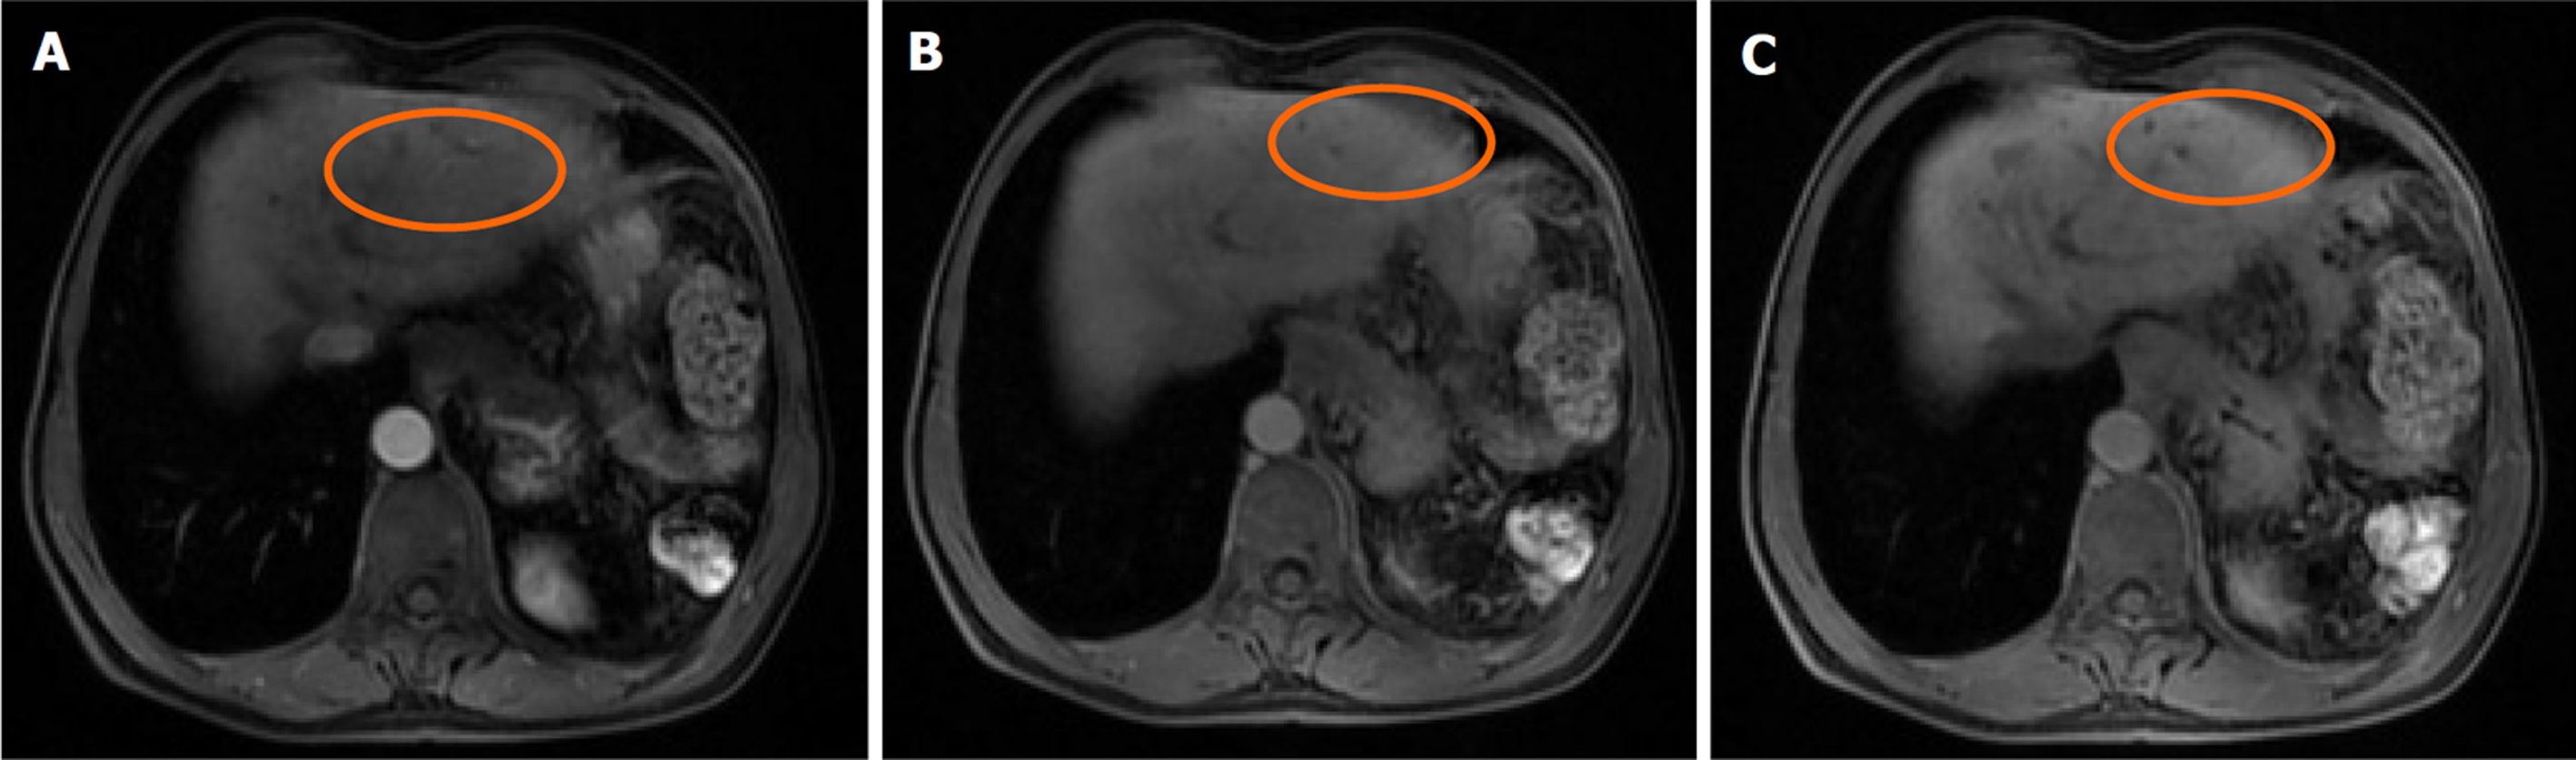

肝脏瞬时弹性测定: CAP 144 dB/m(<238), E 5.8 kPa(<7.3), 未见异常. 心脏超声: 左室假腱索, 二尖瓣+三尖瓣轻度反流. 胸部平扫计算机断层扫描(computerized tomography, CT): 双肺微小结节; 双肺条索灶; 左膈肌升高. 患者行上腹部增强CT示肝脏多发弱强化灶, 不除外肝癌(大者位于左内叶, 截面约1.3 cm×1.1 cm). 肝右叶门静脉期多发异常强化灶, 异常灌注可能. 肝硬化、门脉高压、食管胃底静脉曲张. 门静脉海绵样变. 肝多发囊肿. 胆囊术后; 脾术后. 肝内胆管扩张, 肝门区胆管壁增厚, 炎性病变?下腹部增强CT提示左肾多发结石; 左肾小囊肿; 腹膜后多发淋巴结. 盆腔增强CT提示直肠末端壁稍厚; 盆腔-直肠下段迂曲血管影(图1). 肝脏特异性对比剂增强磁共振(magnetic resonance, MR): 肝脏多发异常信号, 隔顶、左叶病变明显, 考虑肝癌可能. 肝硬化、门脉高压、食管胃底静脉曲张. 门静脉海绵样变. 肝多发囊肿. 胆囊术后、脾术后. 肝内胆管扩张, 肝门区胆管壁增厚, 炎性病变?(图2). 胃镜显示食管胃底静脉曲张(重度)及慢性非萎缩性胃窦炎, 肠镜显示直肠静脉曲张(重度)及结肠多发毛细血管扩张. 患者AFP正常, 影像学呈非典型多灶表现且合并显著门脉高压. 经多学科团队诊疗讨论, 为排除肝细胞癌并厘清基础肝病实体[门窦血管病变(porto-sinusoidal vascular disorder, PSVD)/结节性再生性增生(nodular regenerative hyperplasia, NRH)], 决定行影像引导下肝穿刺活检. 病理示肝板排列不规整, 肝窦灶性扩张, 局灶呈NRH样改变; 静脉束外围薄壁小血管疝入, 直接毗邻肝细胞板(图3). 免疫组化示CD10、CD34、CK19、CK8/18阳性; Masson染色显示汇管区及大血管周围胶原纤维增生, 弹力染色示血管壁弹力纤维增生, 网状纤维染色示局灶肝窦周网状纤维增生. 全基因组测序发现CFTR基因杂合错义变异c.374T>C(p.Ile125Thr).